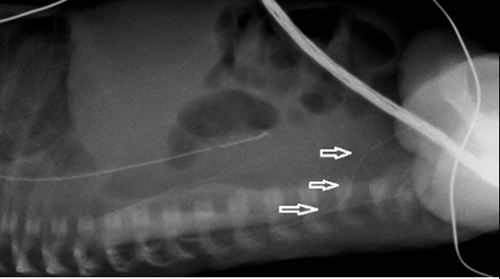

See illustrative x-rays below.

If there are any concerns that this complication has occurred, a lateral x-ray may show the line deviating posteriorly. If possible, seek advice from radiology about further imaging.

Such lines must not be used and the catheter should be removed. These lumbar veins are small, and extravasation of the infusate into the spinal canal may readily occur. This may result in permanent neurological injury and seizures.

![]() |

These two x-rays show PICC lines that have entered the left lumbar vein. In both cases the line has not crossed the midline and lie to the left of the spine. Both X-rays show a kink in the route (arrow) although it is important to note that these kinks were not apparent on the initial x-rays and this feature cannot be relied upon |

This lateral x-ray shows a PICC line in the left lumbar vein taking a posteriorly deviated route (arrows). The correct route would show the line continuing to lie anterior to the spine. | |